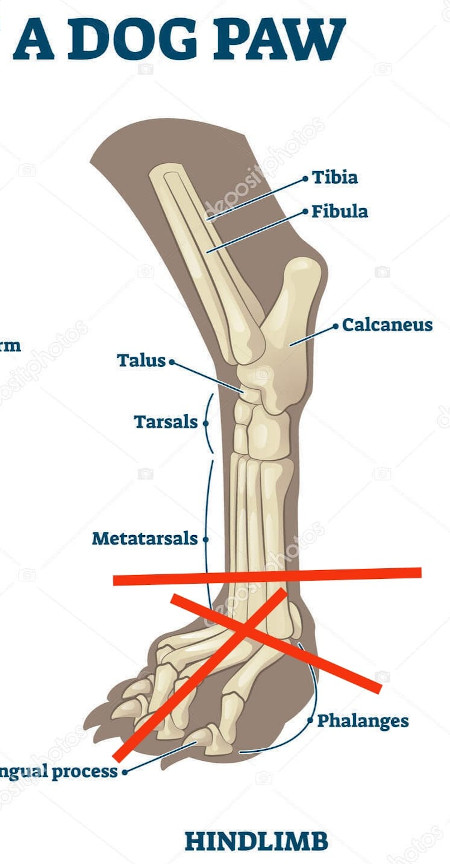

| Bemerkungen | Ellie fehlt am linken Hinterbein der Fuss/die Pfote |

Ellie ist ca. 1 Jahr alt (Stand 08/2024) und hat bereits eine bewegte Vergangenheit hinter sich. Nach 5 Tagen intensiver Versuche konnte sie endlich von der Strasse gerettet werden, wo sie hungrig, durstig und in einem schlechten gesundheitlichen Zustand allein und orientierungslos umherirrte. Elli war von Flöhen und Zecken geplagt und stark abgemagert, doch trotz all dieser Herausforderungen zeigt sie einen unglaublichen Lebenswillen. Elli hat ein Handicap: Ihr fehlt ein Fuß am Hinterbein. Ob dies auf einen Unfall oder eine angeborene Fehlbildung zurückzuführen ist, wissen wir nicht. Doch Elli lässt sich davon nicht einschränken! Sie zeigt sich flink und steckt voller Energie. Ellie kommt erstaunlich gut mit ihrem Bein zurecht, es stört sie in keiner Weise und sie kann problemlos laufen, spielen und sogar rennen. Dennoch benötigt sie einen Schutz für ihren Stummel, entweder eine passende Prothese oder einen gefütterten Silikonschuh. Dies sollte in ihrem neuen Zuhause gründlich tierärztlich abgeklärt werden. Trotz ihrer Vergangenheit ist Elli eine unglaublich liebe, verschmuste und fröhliche Hündin. Sie liebt die Nähe zu Menschen, ist sehr anhänglich und versteht sich gut mit anderen Hunden. Ihre neuen Menschen sollten Freude daran haben, ihr alles ruhig und geduldig beizubringen, was so ein junges Mädel für ihr weiteres Leben als Familienhündin wissen muss. Ebenso sollten sich die neuen Besitzer bewusst sein, dass ein Hund nicht nur Freude, sondern auch jede Menge Arbeit und Verantwortung mit sich bringt, damit Ellie sich zu einer tollen Begleiterin entwickeln kann. Für unsere Herzensbrecherin suchen wir ein liebevolles, fürsorgliches und dauerhaftes Zuhause, wo sie nebst viel Spass auch abwechslungsreiche Spaziergänge erleben darf, wo sie artgerecht ausgelastet wird und täglich die Zuwendung und Pflege bekommt die sie verdient. Wer erfüllt den Traum von unserer Zuckerschnute Ellie und gibt ihr trotz ihres kleinen Handicaps die Chance ein treues Familienmitglied zu werden?